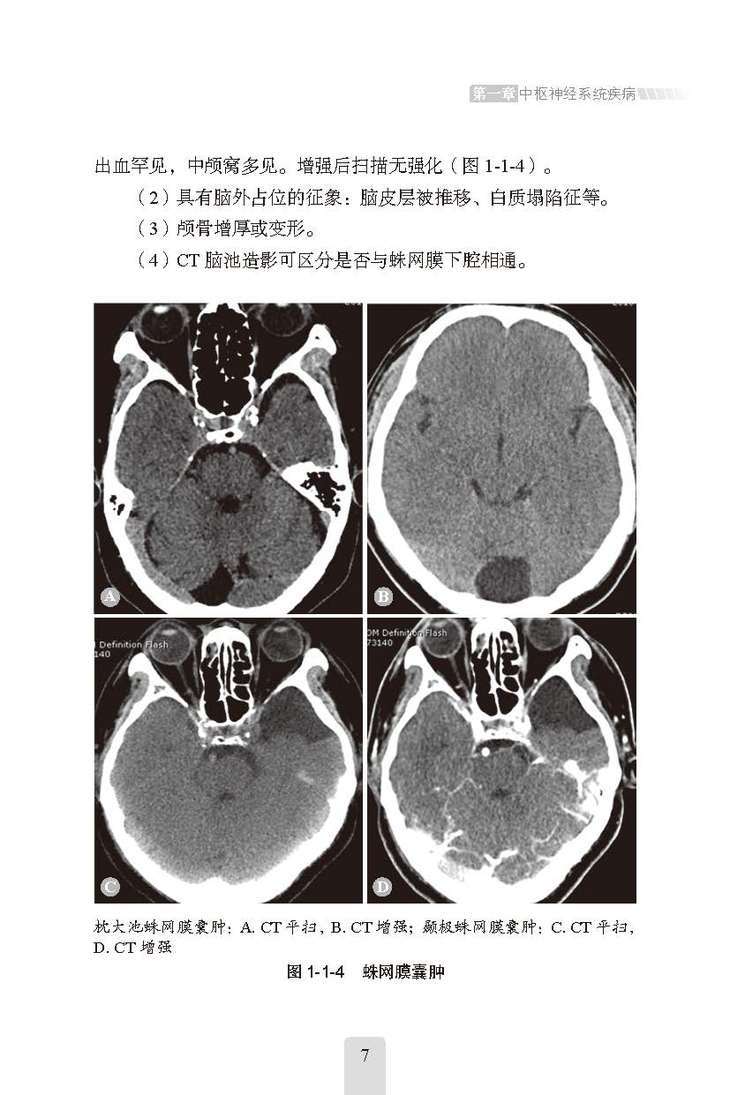

全书共9章、52节,主要讲述了中枢神经系统疾病、头颈五官系统疾病、呼吸系统疾病、循环系统常见疾病、消化系统常见疾病、泌尿系统与肾上腺疾病、腹膜后间隙及腹腔内病变、生殖系统与乳腺常见疾病、骨关节系统疾病,从每种疾病的“影像学检查方法选择”“临床概述”“影像学特点”和“鉴别诊断”等方面进行论述,详细讲解了每种疾病的各个影像学特点,并对易混淆疾病做了全面的鉴别诊断分析,避免了漏诊、误诊的可能。